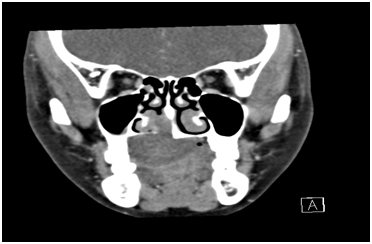

CT Scan of the maxilla revealed erosion of the right half of the hard palate with intranasal extension into the floor of the right nostril with erosion of the adjustant part of the medial wall of the right maxillary antrum upto the base of pterygoid plates and medially the inferior part of the bony part of the nasal septum on that side (Figure 2 & 3). The soft palate was pushed in to the oropharynx. Punch biopsy was taken which suggested Myoepithelioma of minor salivary gland. All preoperative blood and urine investigation was done which were within normal limits. The patient was intubated nasally with endotracheal tube and wide local excision of the mass was done. The tumor was dissected from the nasal mucosa. The excised mass was about 4.5x 3 x2.5cms (Figure 4) and send for histopathological examination. An obturator was given postoperatively.

Figure 2 CT scan showing tumor encroaching nasal floor.

Figure 3 CT scan showing perforation of palatine bone and displacement of tongue and soft palate.